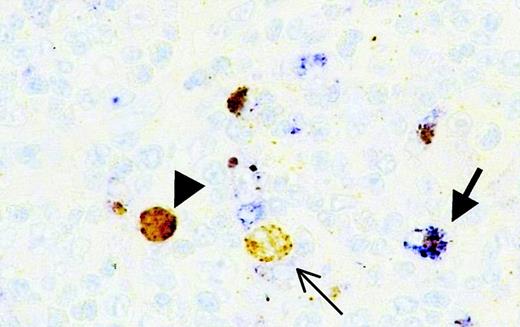

In all patients with HD, active caspase 3 was detected as nuclear staining in a minority of reactive lymphocytes, serving as a positive internal control. In most patients strong, primarily nuclear, staining of active caspase 3 was detected in H/RS cells. Cytoplasmic staining was also observed but nearly always as granular staining in cells with a macrophagelike morphology. Double staining with anti-CD68 confirmed that this cytoplasmic staining was indeed nearly always restricted to macrophages representing mostly phagocytosed nuclear apoptotic debris (Figure 1). Double staining with CD30 or CD15 with either active caspase 3 or PARP/p89 was unsuccessful, probably because of the rapid disappearance of both markers early in apoptosis.

Detection of active caspase 3–expressing neoplastic cells in HD in combination with CD68.

Double staining of active caspase 3 (brown) and CD68 (blue) indicates that nearly all active caspase 3–positive cytoplasmic staining is restricted to CD68-positive macrophages. (arrow) Macrophage containing active caspase 3-positive debris. (arrowhead) Active caspase 3–positive. CD68− H/RS cell with exclusive cytoplasmic staining (thin arrow). Original magnification × 630.